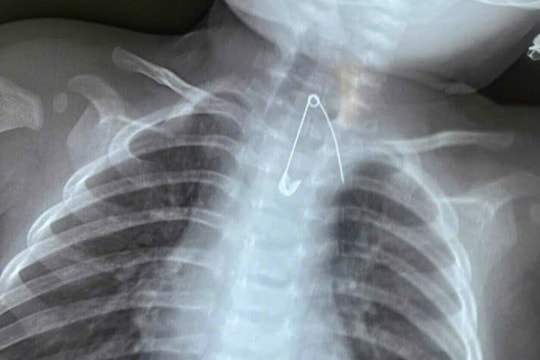

Bé 14 tuổi ho khan kéo dài, gia đình sốc khi bác sĩ lấy ra dị vật bên trong cơ thể

Bị hóc khi ăn hoa quả bé H. xuất hiện cơn ho sặc sụa, tức ngực nhưng chỉ sau vài phút thì hết. Không ngờ trong suốt 13 tháng mới phát hiện bí mật bên trong.